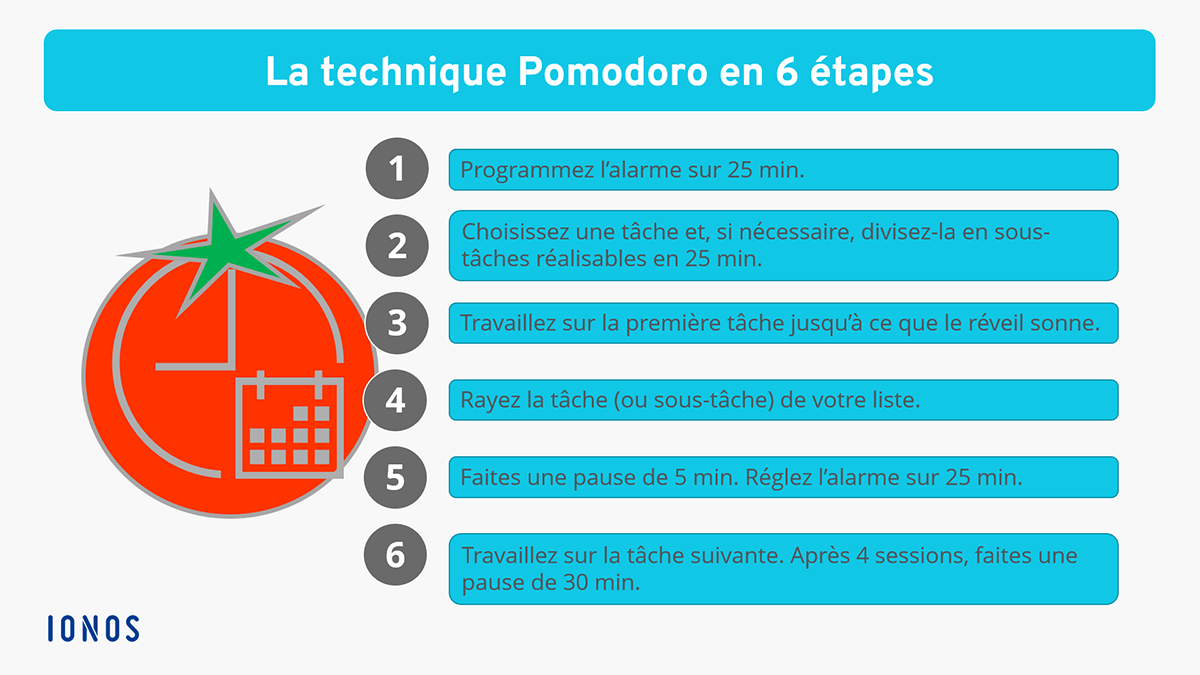

► La

procrastination est le fait de toujours reporter au lendemain ce

qu’on pourrait et/ou devrait faire le jour même. – Cela concerne les activités routinières mais aussi celles qui devraient être prioritaires. → Ils commencent quelque chose pour aussitôt zapper vers autre chose de nouveau, finalement souvent sans rien achever. – A la fin de la journée, ils n’ont rien fait ou n’ont pas fait ce qui était prioritaire, et certains sont quand même très fatigués par cette agitation cognitive et/ou comportementale. ► La principale cause de la procrastination est le manque d’attention qui peut être due à une activité pas assez motivante et qui ne respecte pas leurs besoins, valeurs et talents. – C’est aussi souvent lié à différentes formes de peurs et d’anxiété (peur de s’affirmer, peur de faire des mauvais choix), à un évitement d’une émotion désagréable associée à la tâche, à un perfectionnisme exagéré pouvant être lié à un manque de confiance en soi (peur de ne pas faire assez bien, peur de décevoir ou d’avoir une remontrance) et à un besoin de trouver d’autres motivations plus fortes. – Citons aussi la difficulté de décomposer la tâche en actions élémentaires, exécutées en mode séquentiel, ce qui permettrait de la rendre plus simple à réaliser. ► Mais surtout cela devient au fil du temps des habitudes comportementales et cognitives, et qui peuvent commencer très tôt. – En effet l’enfant TDAH n’a pas d’autres système de défense que de faire trainer la tâche quand on lui demande de faire quelque chose de non motivant, nourrissant du même coup son tempérament rebelle ou son sentiment d’injustice. – Pour d’autres, notamment les enfants précoces, leur facilité à travailler était telle lorsqu’ils étaient dans les petites classes ou encore aujourd’hui quand ils font quelque chose qui les intéresse, qu’ils ne supportent pas la moindre difficulté à se concentrer et préfèrent aller vers quelques chose qui leur procure plus de plaisir au lieu de terminer ce qu’ils ont commencé. ⇒ Cela peut concerner une addiction ou plus simplement aller toujours vers la nouveauté (scanneur) ou la multi-activités (slasheur). ► Il s’en suit à l’âge adulte de grosses difficultés d’organisation pour arriver à un objectif ou assurer le quotidien, ce qui peut entrainer des problèmes financiers à terme. – La plupart n’arrivent pas à planifier, mais bizarrement certains sont au contraire de grands planificateurs, pour se rassurer face à leur difficulté de passer à l’action, donc ça n’avance pas non plus. – Certains se déclarent même des champions de l’organisation, car ils ont appris à se sur-adapter du fat de leurs faiblesses. Donc, ils planifient, préparent trop, essaient de prévoir tout, ou se passionnent pour les outils d’organisation (agenda, to do list), mais vont quand même procrastiner pour passer à la toute première action qu’ils n’ont peut-être pas clairement identifier. – Certains ont donc besoins de tout maitriser avant de se lancer, à cause d’un perfectionnisme lié au manque de confiance en soi, il s’en suit alors souvent de longues recherches sur internet par exemple, juste pour se rassurer. – Beaucoup ont du mal à décomposer un objectif complexe en tâches unitaires et séquentielles, à mettre les bonnes priorités et identifier la toute première action qui pourrait être peut-être de se faire conseiller par quelqu’un. ► Ils n’accrochent pas dans les activités routinières, ont du mal à se fixer des habitudes, des rituels ou des automatismes qui pourraient leur simplifier la vie, sauf certains qui développent au contraire des comportements quasi obsessionnels pour y remédier. – Ils ont quasiment tous un gros problème avec les formalités administratives, ce qui peut leur faire perdre de l’argent ou les bloquer dans leurs objectifs principaux. – On peut penser que dans les générations précédentes, les adultes TDAH n’avaient pas toutes ces contraintes et vivaient mieux, notamment avec plus d’activités physiques au grand air. ► Beaucoup ont aussi du mal à établir des priorités entre les tâches selon leur importance ou leur urgence. – Certains se dissocient de la réalité en partant fréquemment dans leurs pensées avec une certaine insouciance en attendant d’être dans l’urgence. – D’autres sont très lucides en s’évaluant et en se jugeant en permanence. – Car c’est souvent la double peine pour tout une catégorie de procrastineurs, de type anxieux, car non seulement ils n’avancent pas dans leurs tâches à faire, mais ils y pensent sans arrêt, culpabilisent, même en plein weekend ou il faudrait qu’il fasse un break pour recharger leur batterie d’énergie. ► Des périodes entières de leur vie sont des longues suites d’interruptions, des journées d’hypo-activité, de zapping ou d’hyper-focalisation sans lendemain, ainsi que des actions ou routines addictives. – Mais beaucoup ont pris l’habitude de s’en sortir, tel des acrobates, en faisant les choses au dernier moment, avec de la peur ou de l’anxiété d’anticipation mais qui se transforme souvent comme par magie en stress positif quand la date ou l’heure approche. – A noter qu’il y a une journée mondiale de la procrastination chaque année le 25 Mars. |